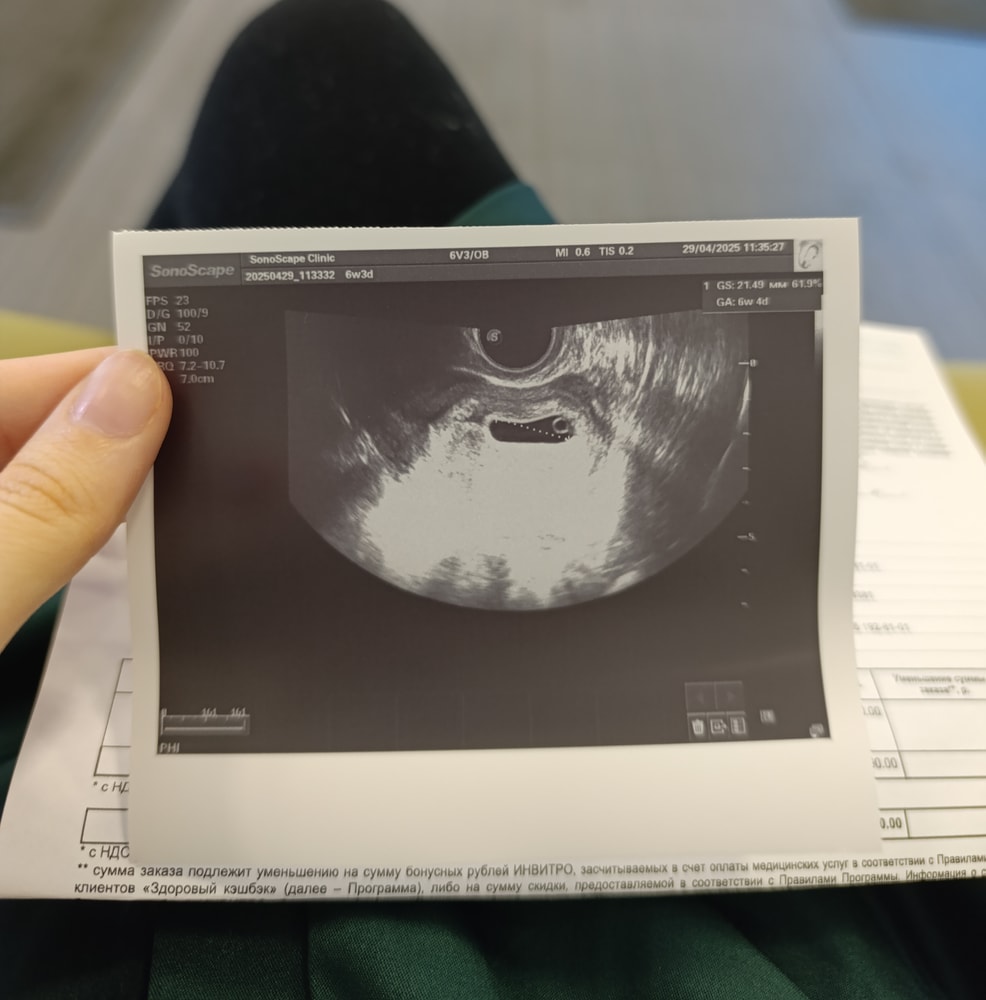

Первое УЗИ

1-ый триместр беременности

Вот и прошло первое узи. Врач сказала, что у нас всё хорошо, беременность маточная, плодное яйцо соответствует сроку, желточный мешочек хороший и даже уже бьётся сердечко. Я безумно счастлива. 🥰